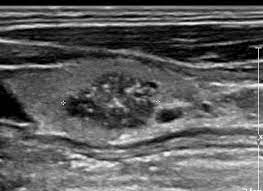

New cards

what thyroid pathology is shown here?

hemorrhagic thyroid cyst